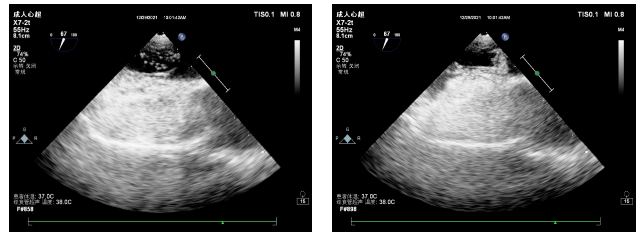

右心声学造影

是一项简便易行的超声心动图检查方法。利用静脉注射手震微气泡生理盐水造影剂,使右心系统显影,通过超声心动图检查,进一步了解右心系统各腔室的解剖结构和血流状况,确定有无心腔内(如卵圆孔未闭、房间隔缺损)或心腔外(如肺动静脉瘘)右向左分流的一种检查手段。